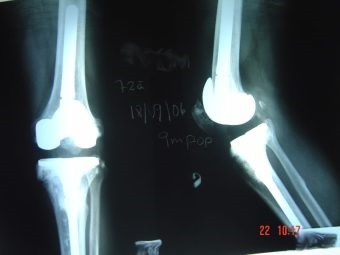

Revisión de prótesis de rodilla

Envíado por Dr. Ricardo Antonio Gómez G.